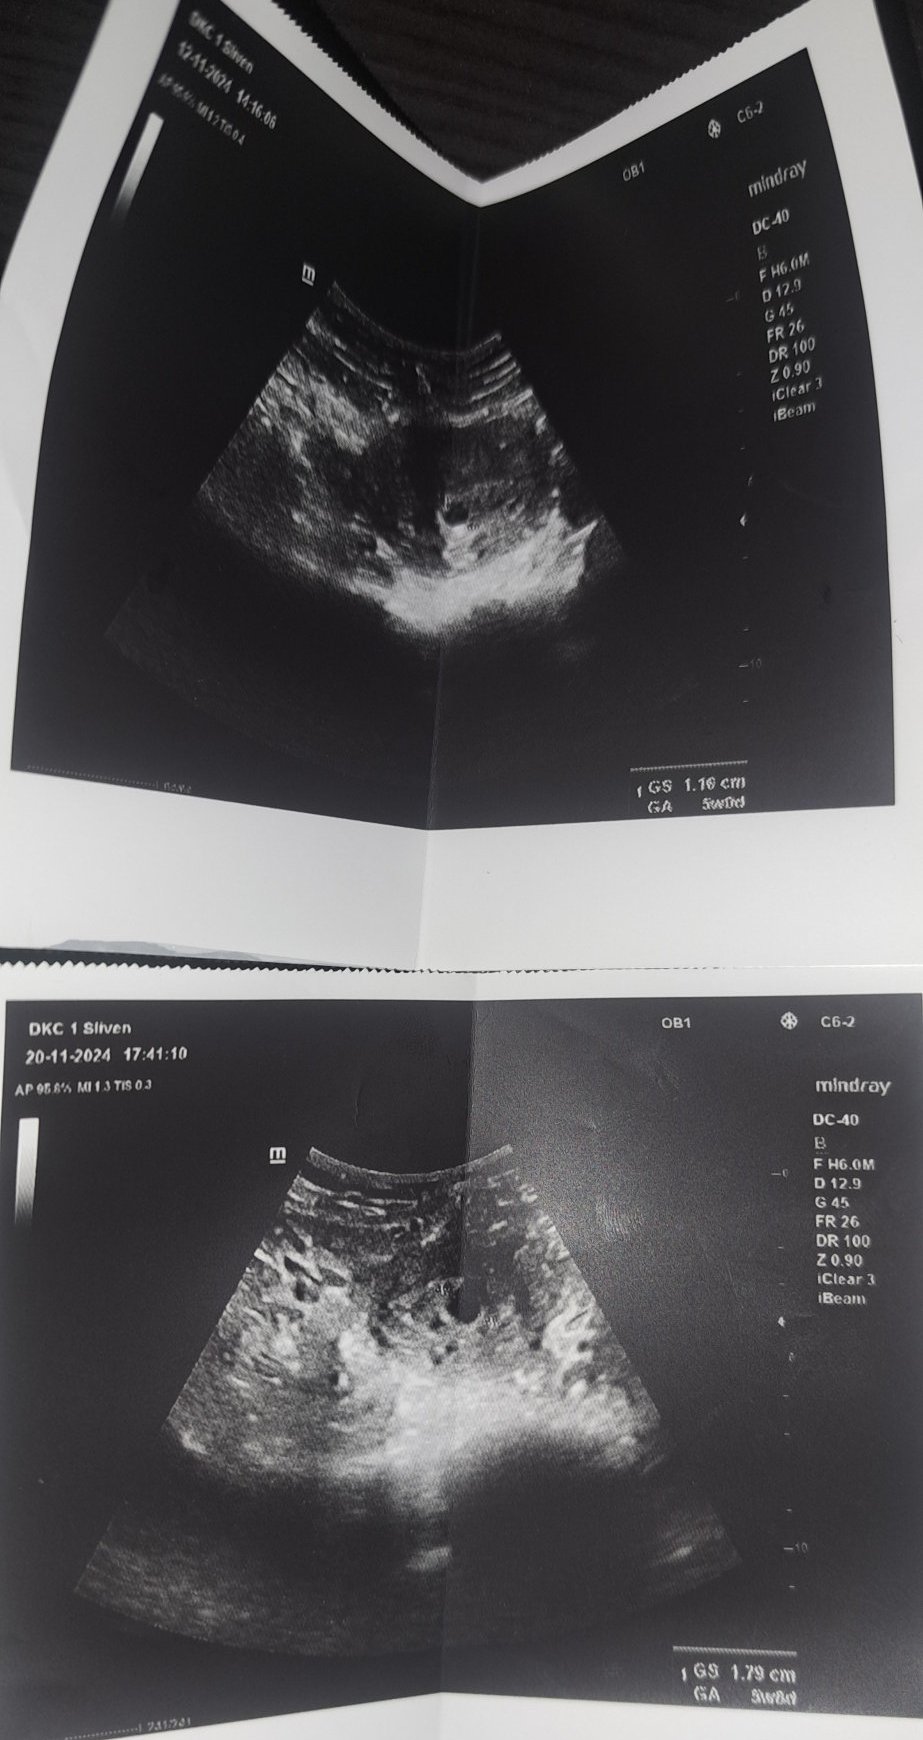

ние тъкмо се израдвахме, че икси процедурата ни беше успешна - след толкова години опити. Сега съм 6 седмици, днес направихме първия ултразвук. Доктора в ин витро клиниката ми направи ултразвук и ме изписа -вече моята генеколожка да ме следи. Той не коментира нищо (ние сме в Германия), само даде снимчиците от ехографа. На тях не се вижда yolk sac (не знам как е на български), и колкото и да гоогълвам - все до статии стигам, че на 6 седмици това вече трябва да е видим иначе бремененноста се брои за негодна. Прикрепям снимчиците - може би някой от вас има опит и може да ми каже повече....Моята гинеколожка може да ме види най-рано след седмица....а до тогава 6те се побарквам....Благодаря предварително!

Има бременност и ембрион. Съвсем нормално изглежда за шеста седмица. Следващата седмица може да чуете и сърцето.Успокойте се и се насладете на бременноста.

Моля за мнение - ходих при 2 лекаря 1 я казва,че е пораснало доста, а другия че е спряло да се развива и не вижда жълтъчно мехурче.

От вчера сутрин съм с кафеникаво зацапване пия фолиева киселина,но шпа,утрогестан- от вчера ми пуснаха но шпа към момента нямам зацапване само сутринта го имах- усещам гърдите си не толкова напрегнати от вчера насам... тази моя бременост ще ме побърка